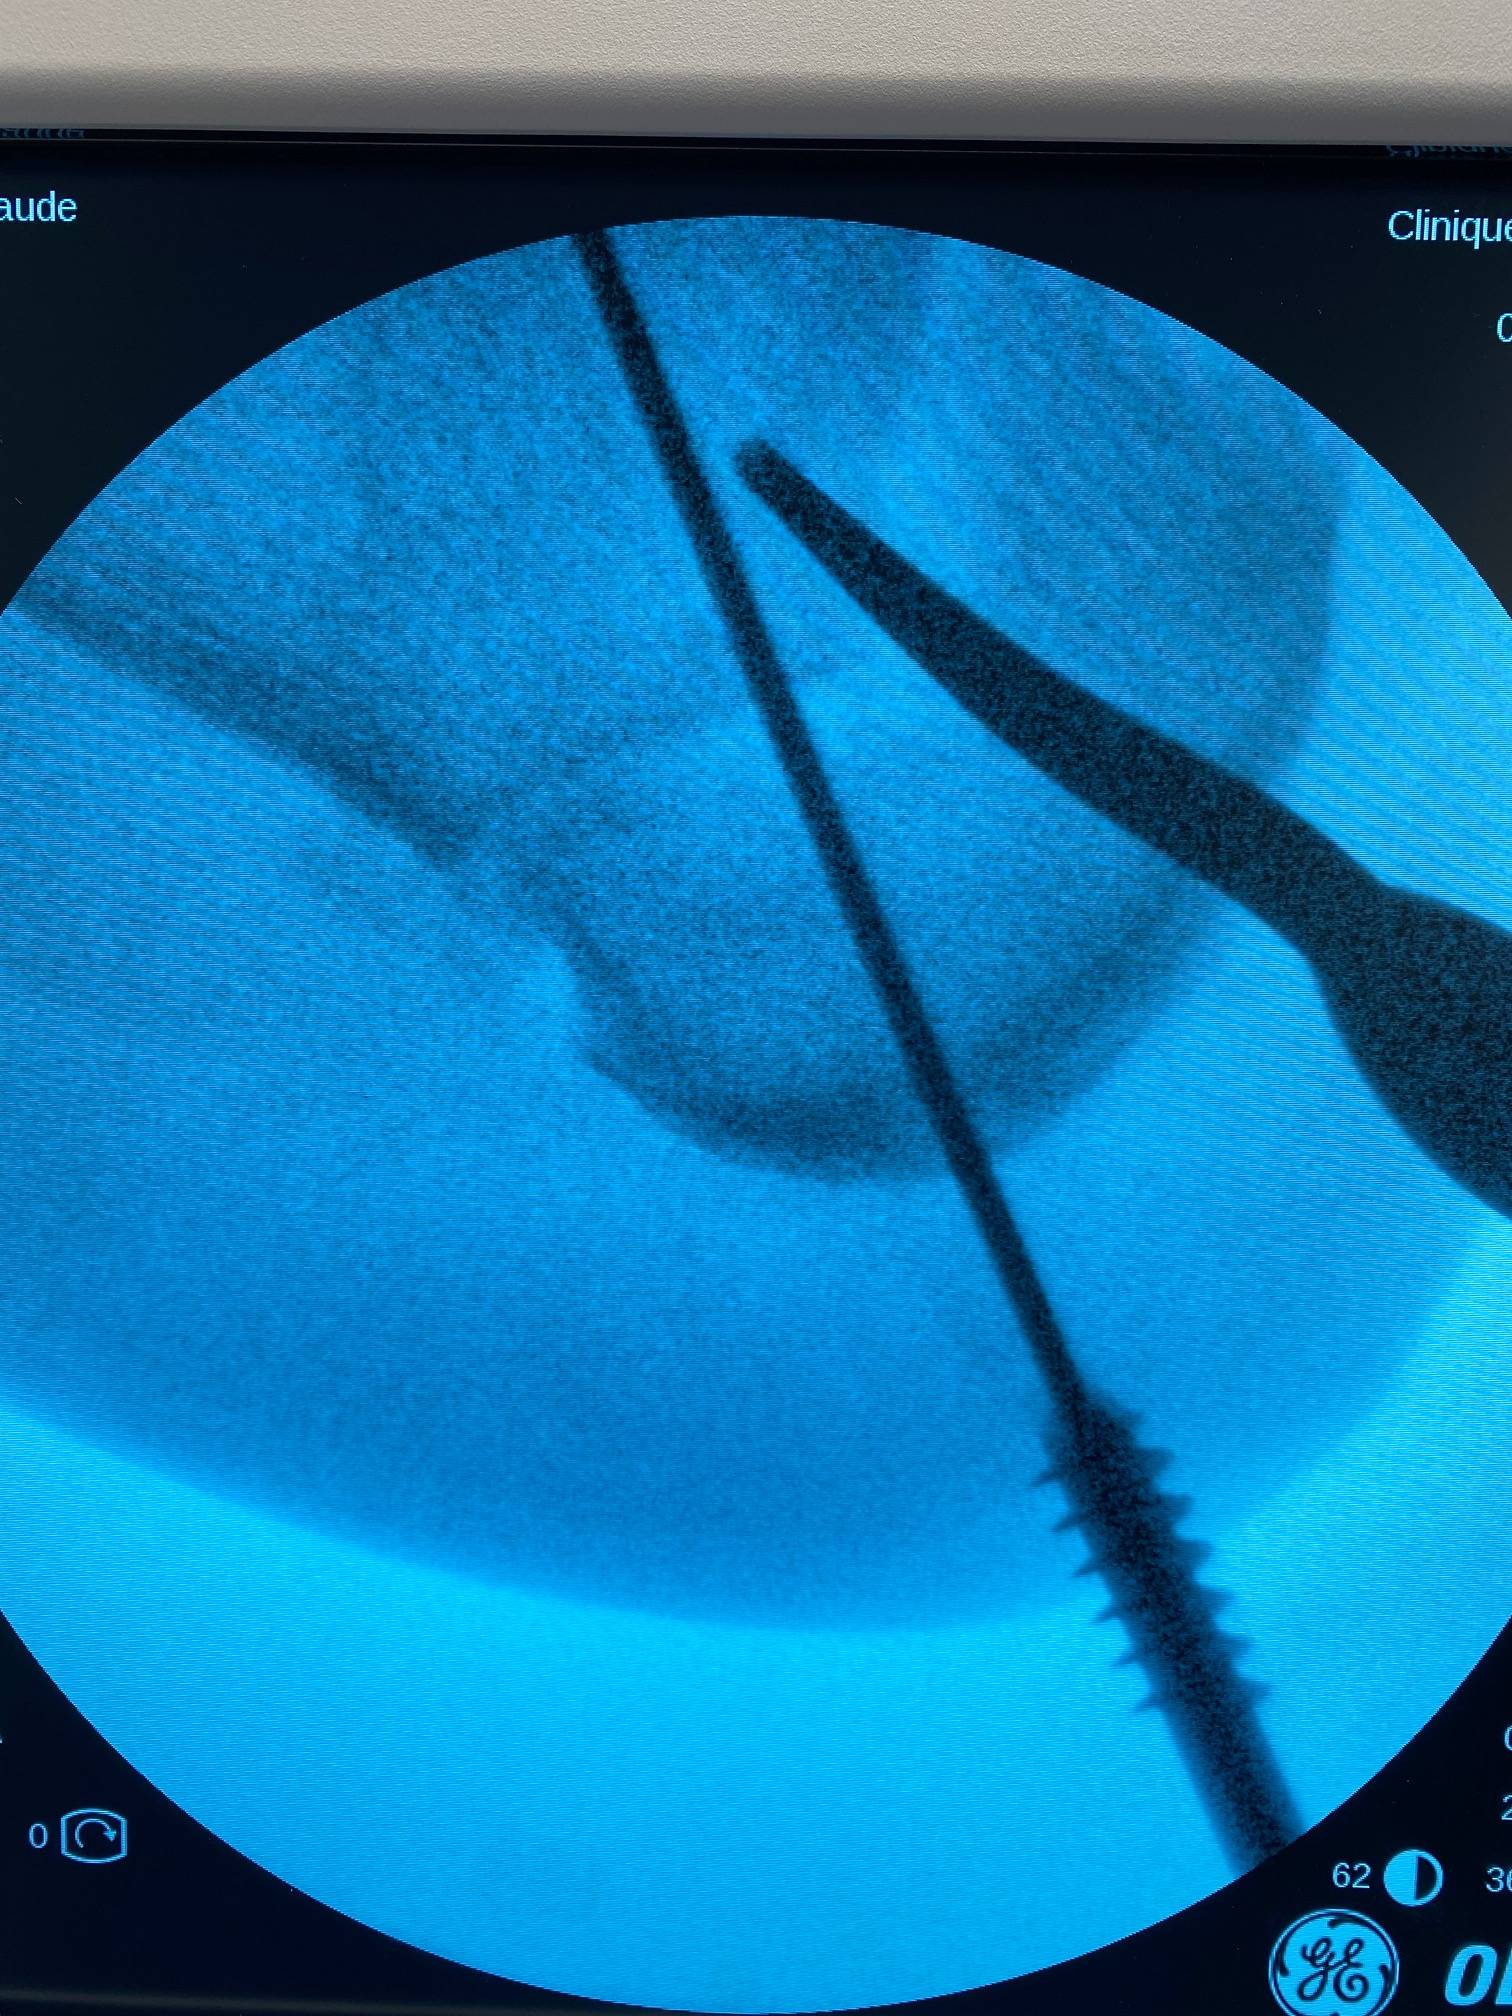

Vous trouverez, ci-dessous, quelques photos d'une ostéotomie calcanéenne de valgisation sur arthrose varisante

Institut de la Cheville et du Pied, bloc opératoire de l'ICP Paris (Clinique Blomet)